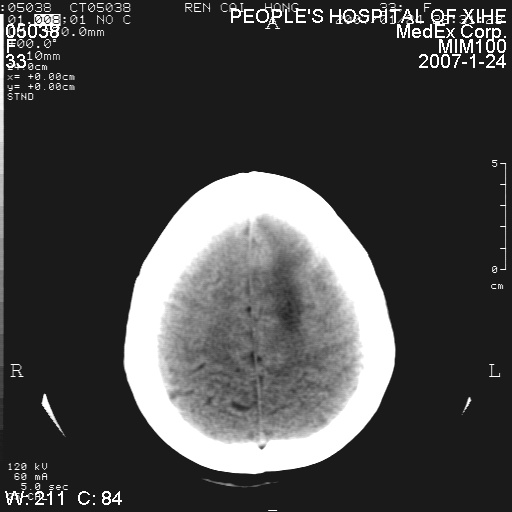

以下是引用卜一在2007-1-25 6:40:00的发言:[br]左侧额叶囊实混杂性病灶,多考虑胶质细胞瘤(ⅱ-ⅲ级),建议增强检查。[br]支持!

以下是引用wwwwtyy在2007-1-25 0:27:00的发言:[br]胶质瘤可能性大,不除外脑白质病变,建议强化

以下是引用xclzq_910在2007-1-25 12:41:00的发言:[br]左额叶条片状低密度灶,考虑占位,建议增强

以下是引用守望可可西里在2007-1-25 0:13:00的发言:[br]左侧额叶囊实混杂性病灶,多考虑胶质细胞瘤(ⅱ-ⅲ级),建议增强检查!